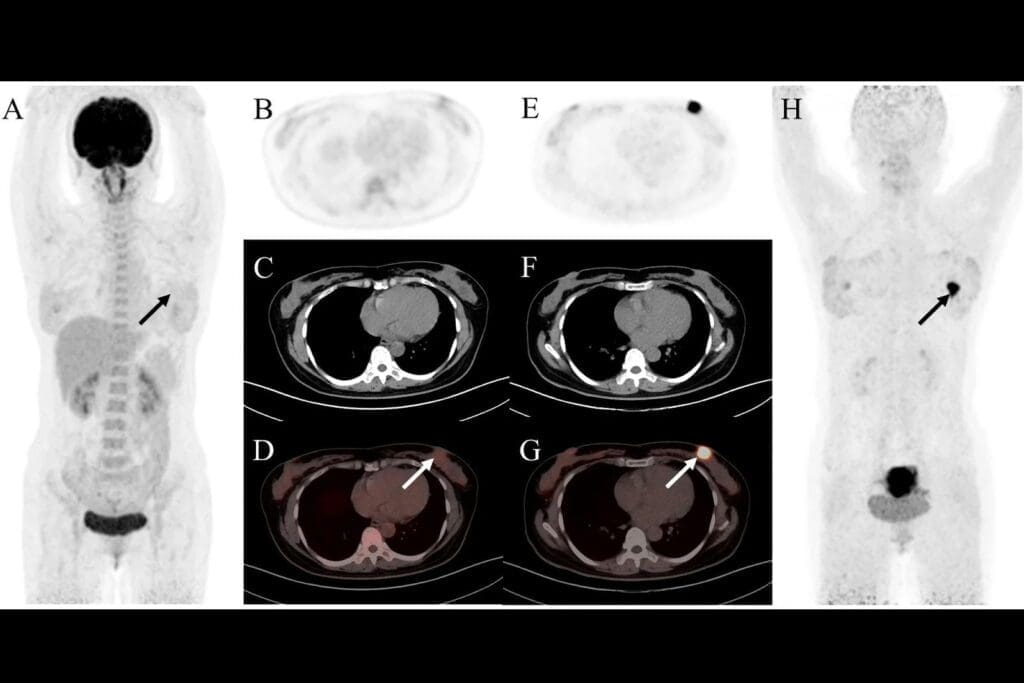

Pyelonephritis Indicators on CT

Pyelonephritis is an infection in the kidney’s pelvis and tissue. A CT urogram shows signs like a bigger kidney, uneven kidney brightness, and swelling around the kidney. These signs help diagnose and understand how serious the infection is.

Acute Pyelonephritis

Acute pyelonephritis is an infection in the kidney, usually from bacteria. On CT urograms, it shows as renal enlargement with patchy or striated nephrograms. You might also see perinephric stranding, which means inflammation spreading beyond the kidney.

Emphysematous pyelonephritis is a severe kidney infection, common in diabetics. CT scans show gas in the renal parenchyma and sometimes in the collecting system or perinephric space. It’s a serious condition that needs quick diagnosis and treatment.

Renal and Perirenal Abscesses

Renal and perirenal abscesses are pus collections in or around the kidney, caused by infections. On CT urograms, they look like low-attenuation masses with rim enhancement. Perirenal abscesses can push against or compress nearby structures.